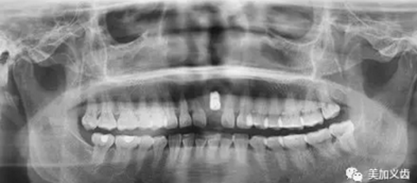

3.牙科CT掃描,種植計劃

頜面部CBCT掃描,頜骨三維建模。在CBCT數(shù)據(jù)處理軟件中標記出重要的神經(jīng)、血管、上頜竇等關鍵解剖標志。將上述CAD/CAM軟件中完成的冠橋CAD數(shù)據(jù)導入CBCT軟件,.STL格式的牙頜模型與DICOM格式的CT牙頜骨模型配準整合,選擇合適的植體,避開重要解剖結構,設計安全的種植體植入位置與角度,實現(xiàn)以生理性修復為導向的種植規(guī)劃。